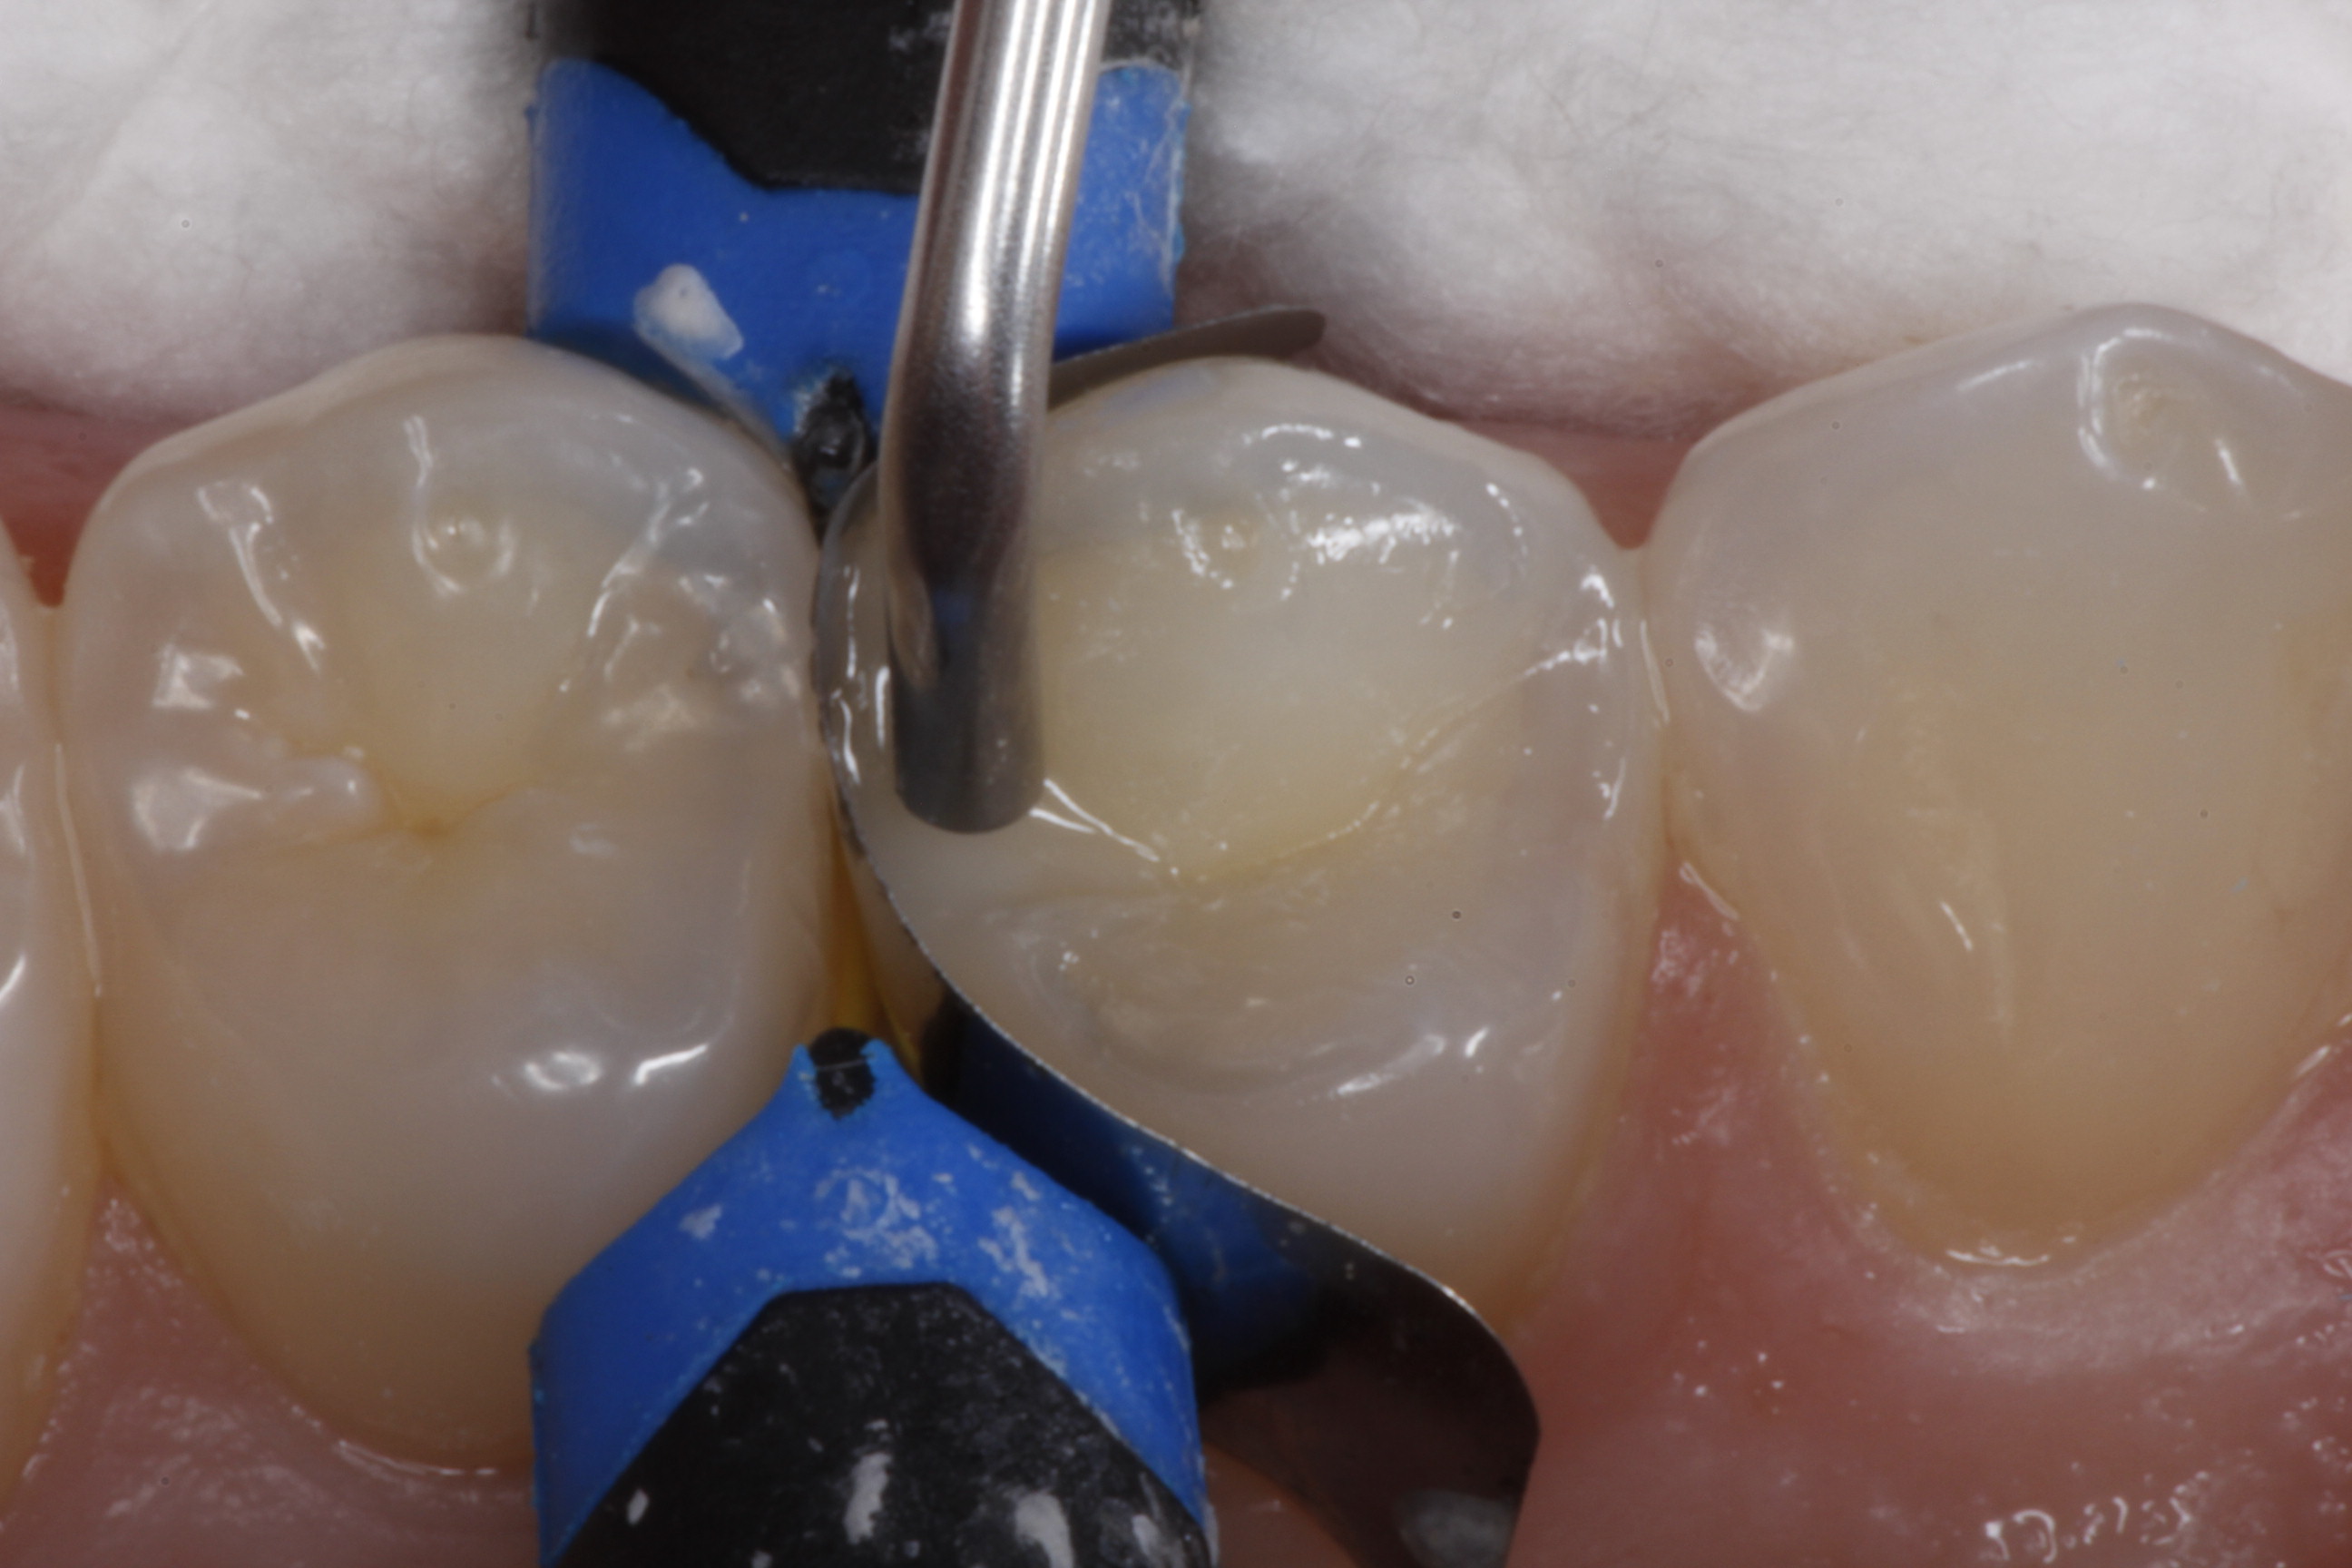

Fig 26. A mesial-occlusal cavity preparation on tooth No. 3 is shown after isolation and placement of a sectional matrix.

Figure 26